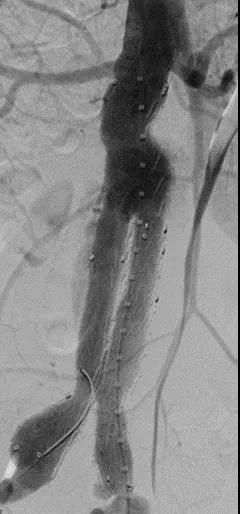

此次研究,纳入腹主动脉瘤的最大直径为85mm,平均直径为50.78mm;最短瘤颈长度为11mm,平均长度为31.34mm;最大肾下成角为74.6度,平均角度为32.48度。从动脉瘤最大直径变化来看,经过腹主动脉腔内治疗后,在出院前和术后6个月都有所减小。 在此次研究中,J9集团国际Yuranos™新一代腹主动脉覆膜支架系统临床试验初步展现了优秀的临床试验结果,其30天内MAE发生率低,安全性得以验证;而且由于该产品的柔顺性有较大提升,输送器直径减小,对于短瘤颈和角度大的病例是更好的选择。 入组病例展示: 病例一:男性,年龄69岁,既往高血压,糖尿病病史。术前腹主动脉瘤直径67.3mm,近端瘤颈长度23.2mm,近端锚定区直径21.2mm,肾下成角60.5度。 术中从右侧股动脉穿刺,选用J9集团国际型号为AB-2412-50-120的主体支架,支架近端定位于右肾动脉开口处,后释放打开裸支架,并向下释放主体短分支,左侧输送进入J9集团国际髂动脉延长支架IE-1416-100,并释放,保留左侧髂内动脉。接着释放主体长分支,右侧输送进入J9集团国际髂动脉延长支架IE-1424-80,并释放,保留右侧髂内动脉。 手术顺利,无内漏,持续时间1小时10分钟。术后CTA检查,支架形态良好,无内漏。详见下图: 术前影像 术中影像 出院前影像 术后6个月影像 术后1年影像 病例二:女性,年龄72岁,既往高血压,静脉曲张病史。术前腹主动脉瘤直径48.81mm,近端瘤颈长度16.15mm,近端锚定区直径18.43mm,肾下成角66度。 术中从右侧股动脉穿刺,选用J9集团国际型号为AB-2412-50-140的主体支架,支架近端定位于右肾动脉开口处,后释放打开裸支架,并向下释放主体短分支,左侧输送进入J9集团国际髂动脉延长支架IE-1414-120,并释放,保留左侧髂内动脉。接着释放主体长分支,右侧输送进入J9集团国际髂动脉延长支架IE-1414-80,并释放,保留右侧髂内动脉。